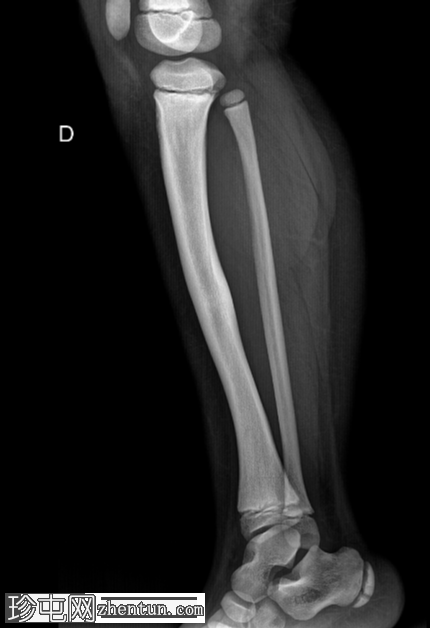

右大腿隐痛持续数日。已知有致密性骨发育不良病史。

年龄:10岁

性别:男

X光片

正面

侧面

弥漫性骨密度增高。

长骨髓质变窄。

右股骨不完全性骨折,骨折后功能不全。

双侧胫骨骨干先前骨折后出现骨重塑。